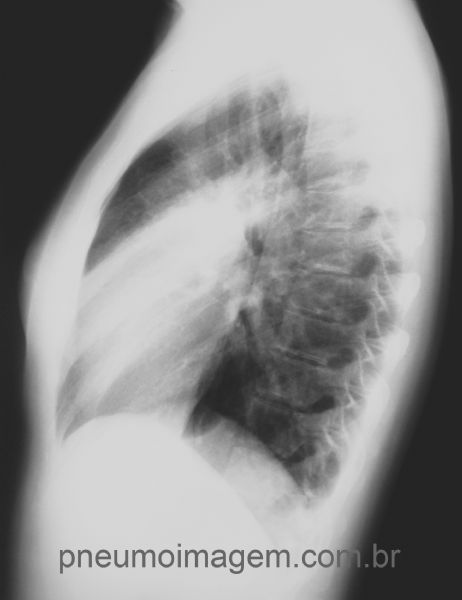

Observe na incidência em perfil a imagem se projetando sobre a sombra cardíaca.

Radiografia do mesmo paciente após tratamento com levofloxacina por 7 dias: resolução quase completa da opacidade anterior.

Na incidência em perfil pode observar a resolução quase completa da pneumonia após o tratamento.

Chaves: condensação.